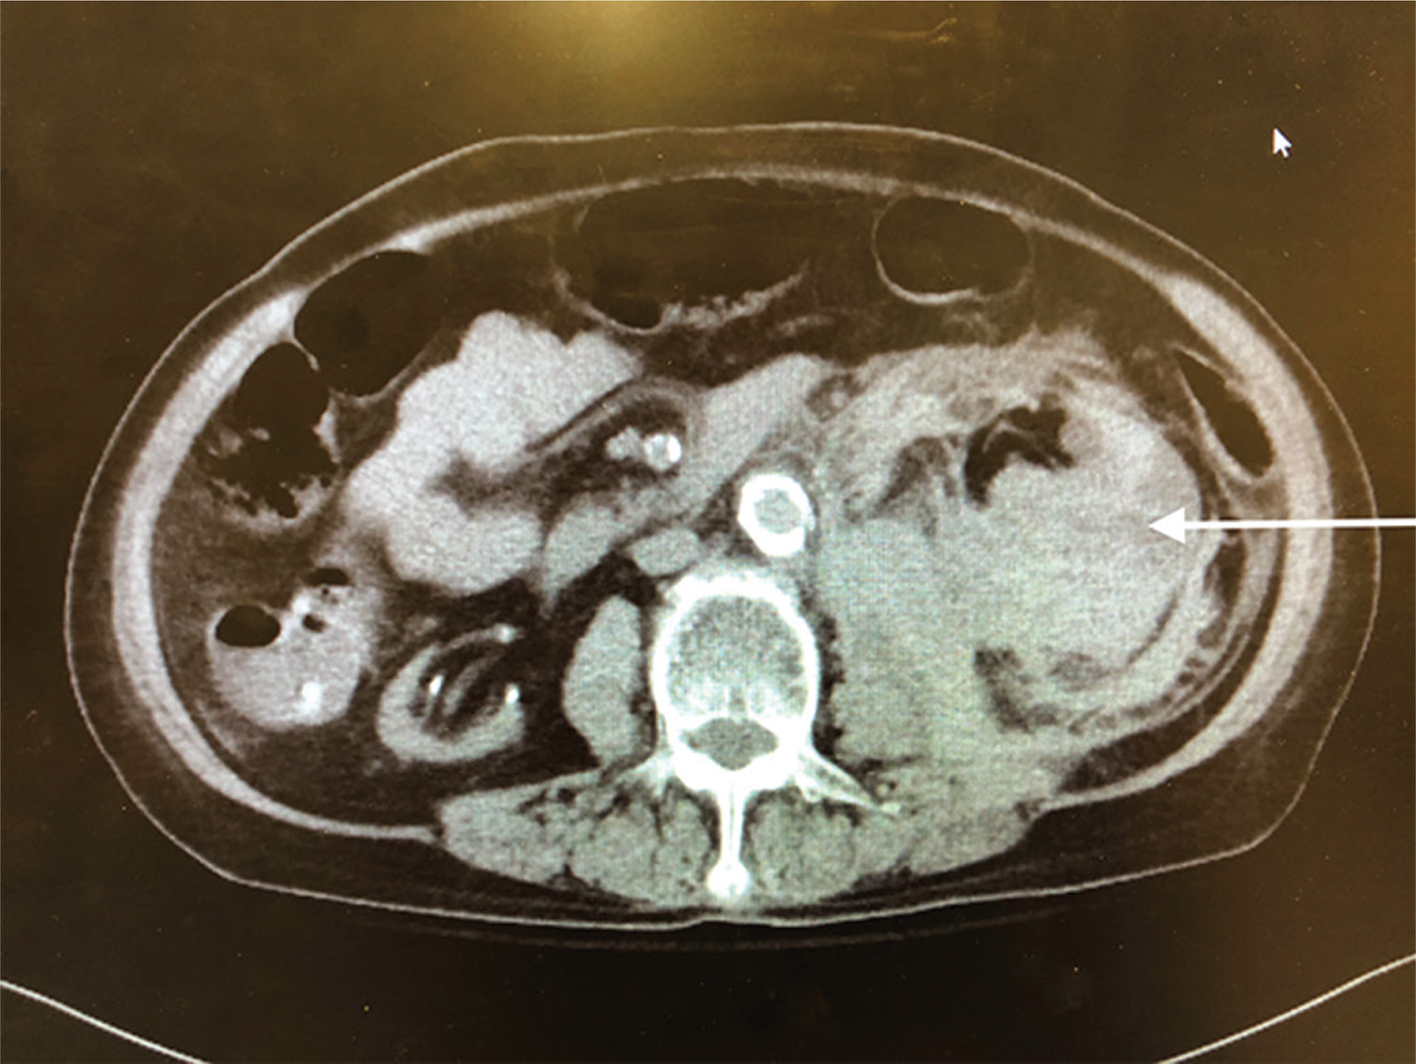

Pathology showed extensive sclerosed glomeruli, marked interstitial inflammation, severe arteriosclerosis, perirenal and renal parenchymal hemorrhage, severe renal artery atherosclerosis, and ACKD. Figurers 1 and 2 show the enlarged left kidney with massive retroperitoneal hemorrhage on CT scan.

Fig 1

Figure 1: Axial CT image of left retroperitoneal hemorrhage.The arrow refers to the large retroperitoneal hematoma.